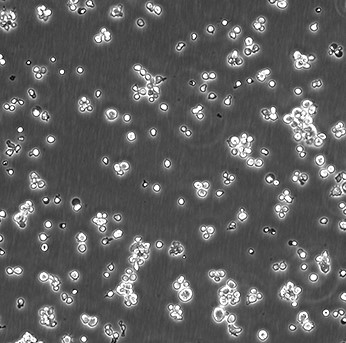

EB-3

EB-3; Epstein-Barr-3; GM04679

90%RPMI-1640+10% FBS

Temperature: 37°C ; Carbon dioxide (CO₂), 5%

贴壁细胞